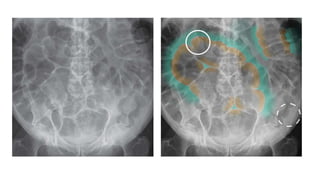

PELVIC FRACTURE

Three rings :

Pelvic ring – paired ilium ,

ischium and pubic bones along

with sacrum

Ring of bone surrounding the

right obturator foramen

left obturator foramen

If you see a fracture in one part

of the ring , look for the second

fracture.

It is impossible to have a